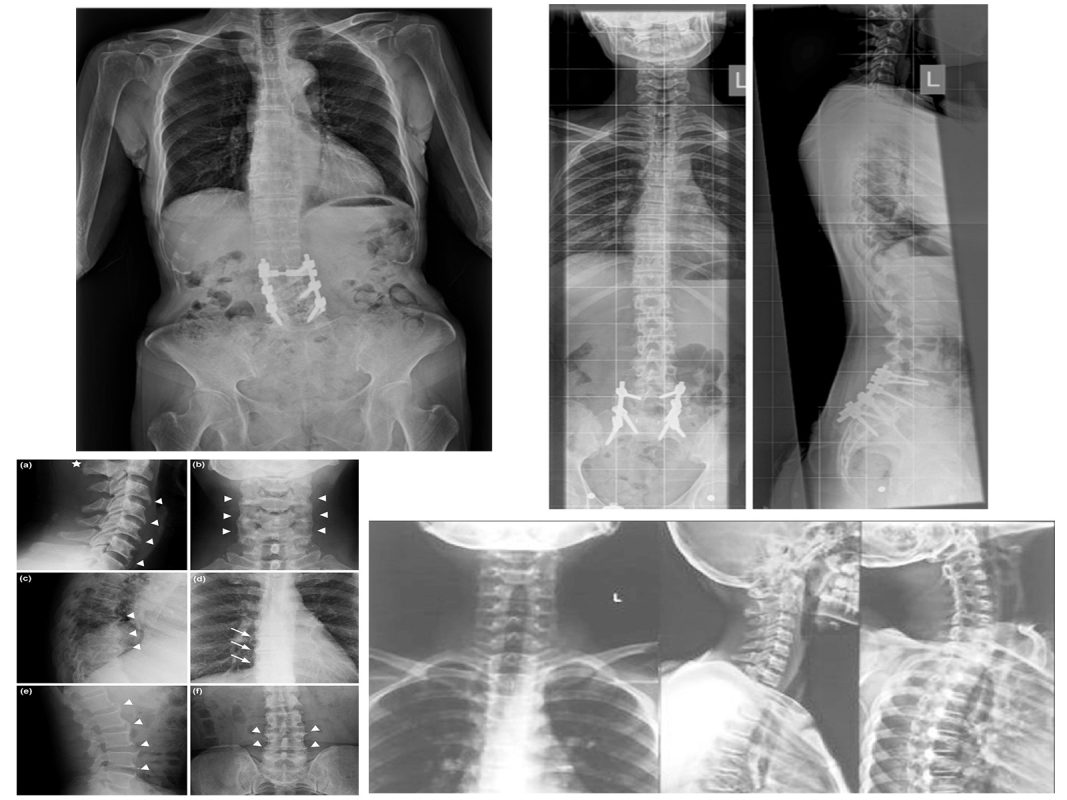

Chụp X-quang toàn bộ cột sống: Phát hiện sớm các bệnh lý xương khớp Chụp X quang toàn bộ cột sống là gì? Chụp X-quang toàn bộ cột sống là phương pháp chẩn đoán hình ảnh sử dụng tia X để ghi lại hình ảnh các cấu trúc xương của cột sống. Phương pháp này […]